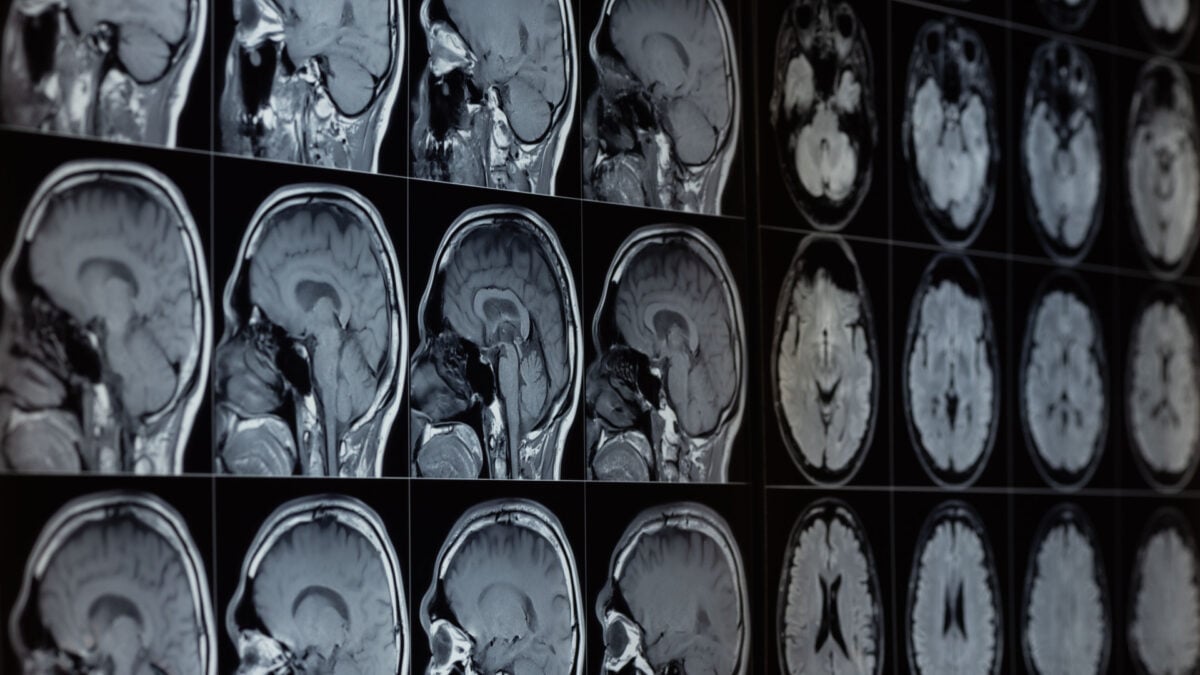

The brains of individuals with Alzheimer’s show multiple differences compared to healthy brains. Notably, they have elevated levels of misfolded amyloid beta and tau proteins, which normally serve vital functions. However, it’s not just these proteins that change in Alzheimer’s, and during their research into other neurological alterations, the Harvard team made a significant finding.

Utilizing existing projects that gathered postmortem tissue samples, they analyzed around 30 different metals in the brains of individuals who had died with varying cognitive abilities. Their observations indicated that lithium levels were the sole major difference: those with healthy cognitive function had higher lithium, while those with Alzheimer’s exhibited much lower levels. Remarkably, this reduction in lithium was also visible in individuals who had only mild memory issues prior to their passing.